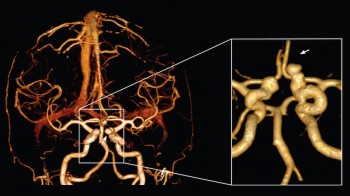

Koronarna CT angiografija

Kardiovaskularne bolesti su ubica broj jedan u današnjem svijetu i odnose svake godine više života nego sve maligne bolesti zajedno. Koronarna bolest je najčešće uzrokovana aterosklerozom (stvaranjem plakova u zidu krvnih žila uzrokojući njihvo suženje). Donedavno, nije postojao neinvazivni način da se direktno analiziraju koronarne arterije na prisustvo aterosklerotskih promjena. Razvoj tehnologije višeslojnog CT-a (MSCT/MDCT) omogućio je detaljno trodimenzionalno prikazivanje kucajućeg srca u toku jednog zadržavanja daha. U našem dijagnostičkom centru nudimo ovu tehniku pregleda koronarnih arterija, na multi-slice aparatu, s najmodernijim softverom i minimalnom dozom zračenja.

Šta je CT koronarografija?

To je metoda prikaza malih arterija koje hrane srčani mišić, upotrebom CT skenera, koji prikazuje protok krvi u koronarnim arterijama i kompjuterskog softvera da bi se dobio odgovarajući trodimenzionalni prikaz. CT angiografija je neinvazivni način da se prikažu zidovi koronarnih arterija I nadju eventualni aterosklerotski plakovi, što pomaže liječniku u odredjivanju rizika srčanog udara.